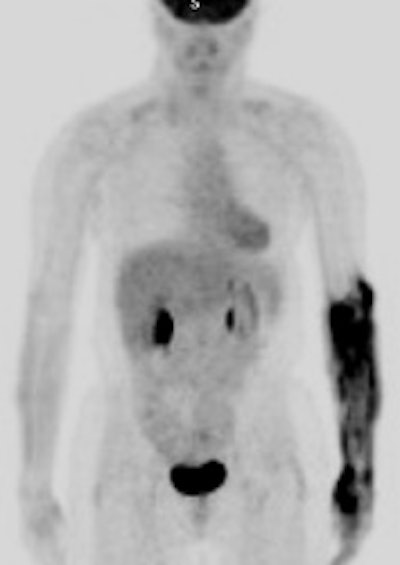

Hyperinsulinemia: The patient below had

a normal glucose level and was injected for an FDG PET

scan. Imaging revealed intense cardiac uptake and a large

about of muscular activity. The findings are consistent

with a hyperinsulinemic state and the patient subsequently

admitted to eating a small breakfast. |